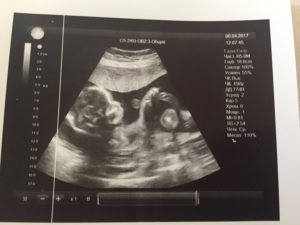

Сначала беременная проходит ультразвуковую диагностику. Процедура полностью безболезненна и безвредна для плода. УЗИ на 2-м скрининге делается для соотношения установленных норм показателей измерения частей тела и органов плода с индивидуальными результатами обследования у беременных.

Врачи в основном смотрят результаты УЗИ на 2-м скрининге. Биохимический анализ крови назначается при особых показаниях, когда у будущей матери выявлены риски на скрининге в первом триместре. В результатах УЗИ 2-го скрининга указывают внешние данные ребенка: размеры всех частей тела, рост, вес, количество плодов в матке.

После анализа внешних данных сонолог переходит к фетометрии, оценке анатомического строения плода при скрининге 2-го триместра. Обследуются кости ребенка, измеряется длина конечностей, определяется состояние внутренних органов и их развитость.